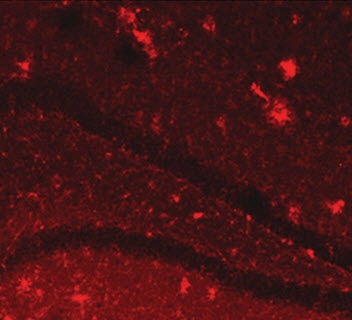

Opening the blood-brain barrier allows the body to remove plaque in the hippocampus